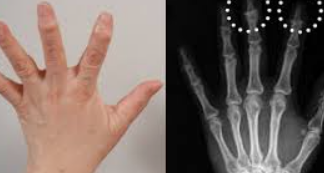

퇴행성 관절염, 일명 '골관절염'은 관절을 보호하는 연골이 닳아 없어지면서 발생하는 질환입니다. 이로 인해 관절의 뼈가 서로 마찰을 일으키며 통증, 부기, 그리고 운동 범위의 제한을 초래합니다. 퇴행성 관절염은 주로 노화와 관련이 있으며, 무릎, 엉덩이, 손, 그리고 척추와 같은 관절에 자주 나타납니다.

증상은 점진적으로 발전하며, 초기에는 운동 후 통증이 나타나기 시작합니다. 시간이 지남에 따라 휴식을 취해도 통증이 지속되며, 관절의 경직과 부기가 동반됩니다. 심한 경우에는 관절의 변형까지 발생할 수 있습니다. 날씨가 추울 때나 습할 때 통증이 더 심해지는 것을 경험할 수도 있습니다.